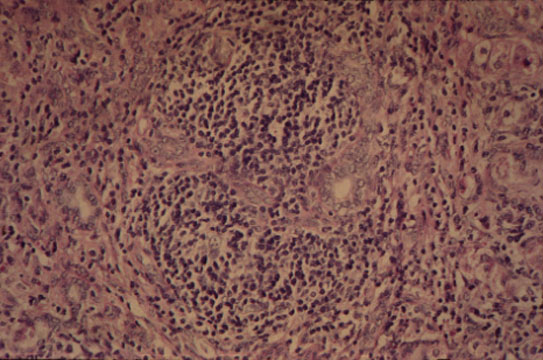

Hepatitic bile duct lesion

(Poulsen Christoffersen lesion)

Fig 62 - HEPATITIC BILE DUCT LESION (Poulsen-Christoffersen Lesion): Lymphoid nodule surrounding a damaged portal bile duct.